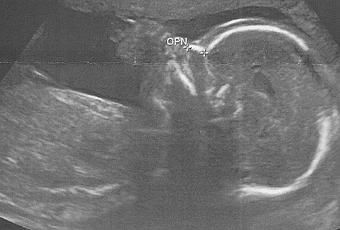

Mais avant je voulais juste vous dire que tout va bien, Petit pois se porte bien : 24 cm pour 416 grammes.

L'écho n'a rien révélé de spécial hormis son sexe : c'est un p'tit mec !